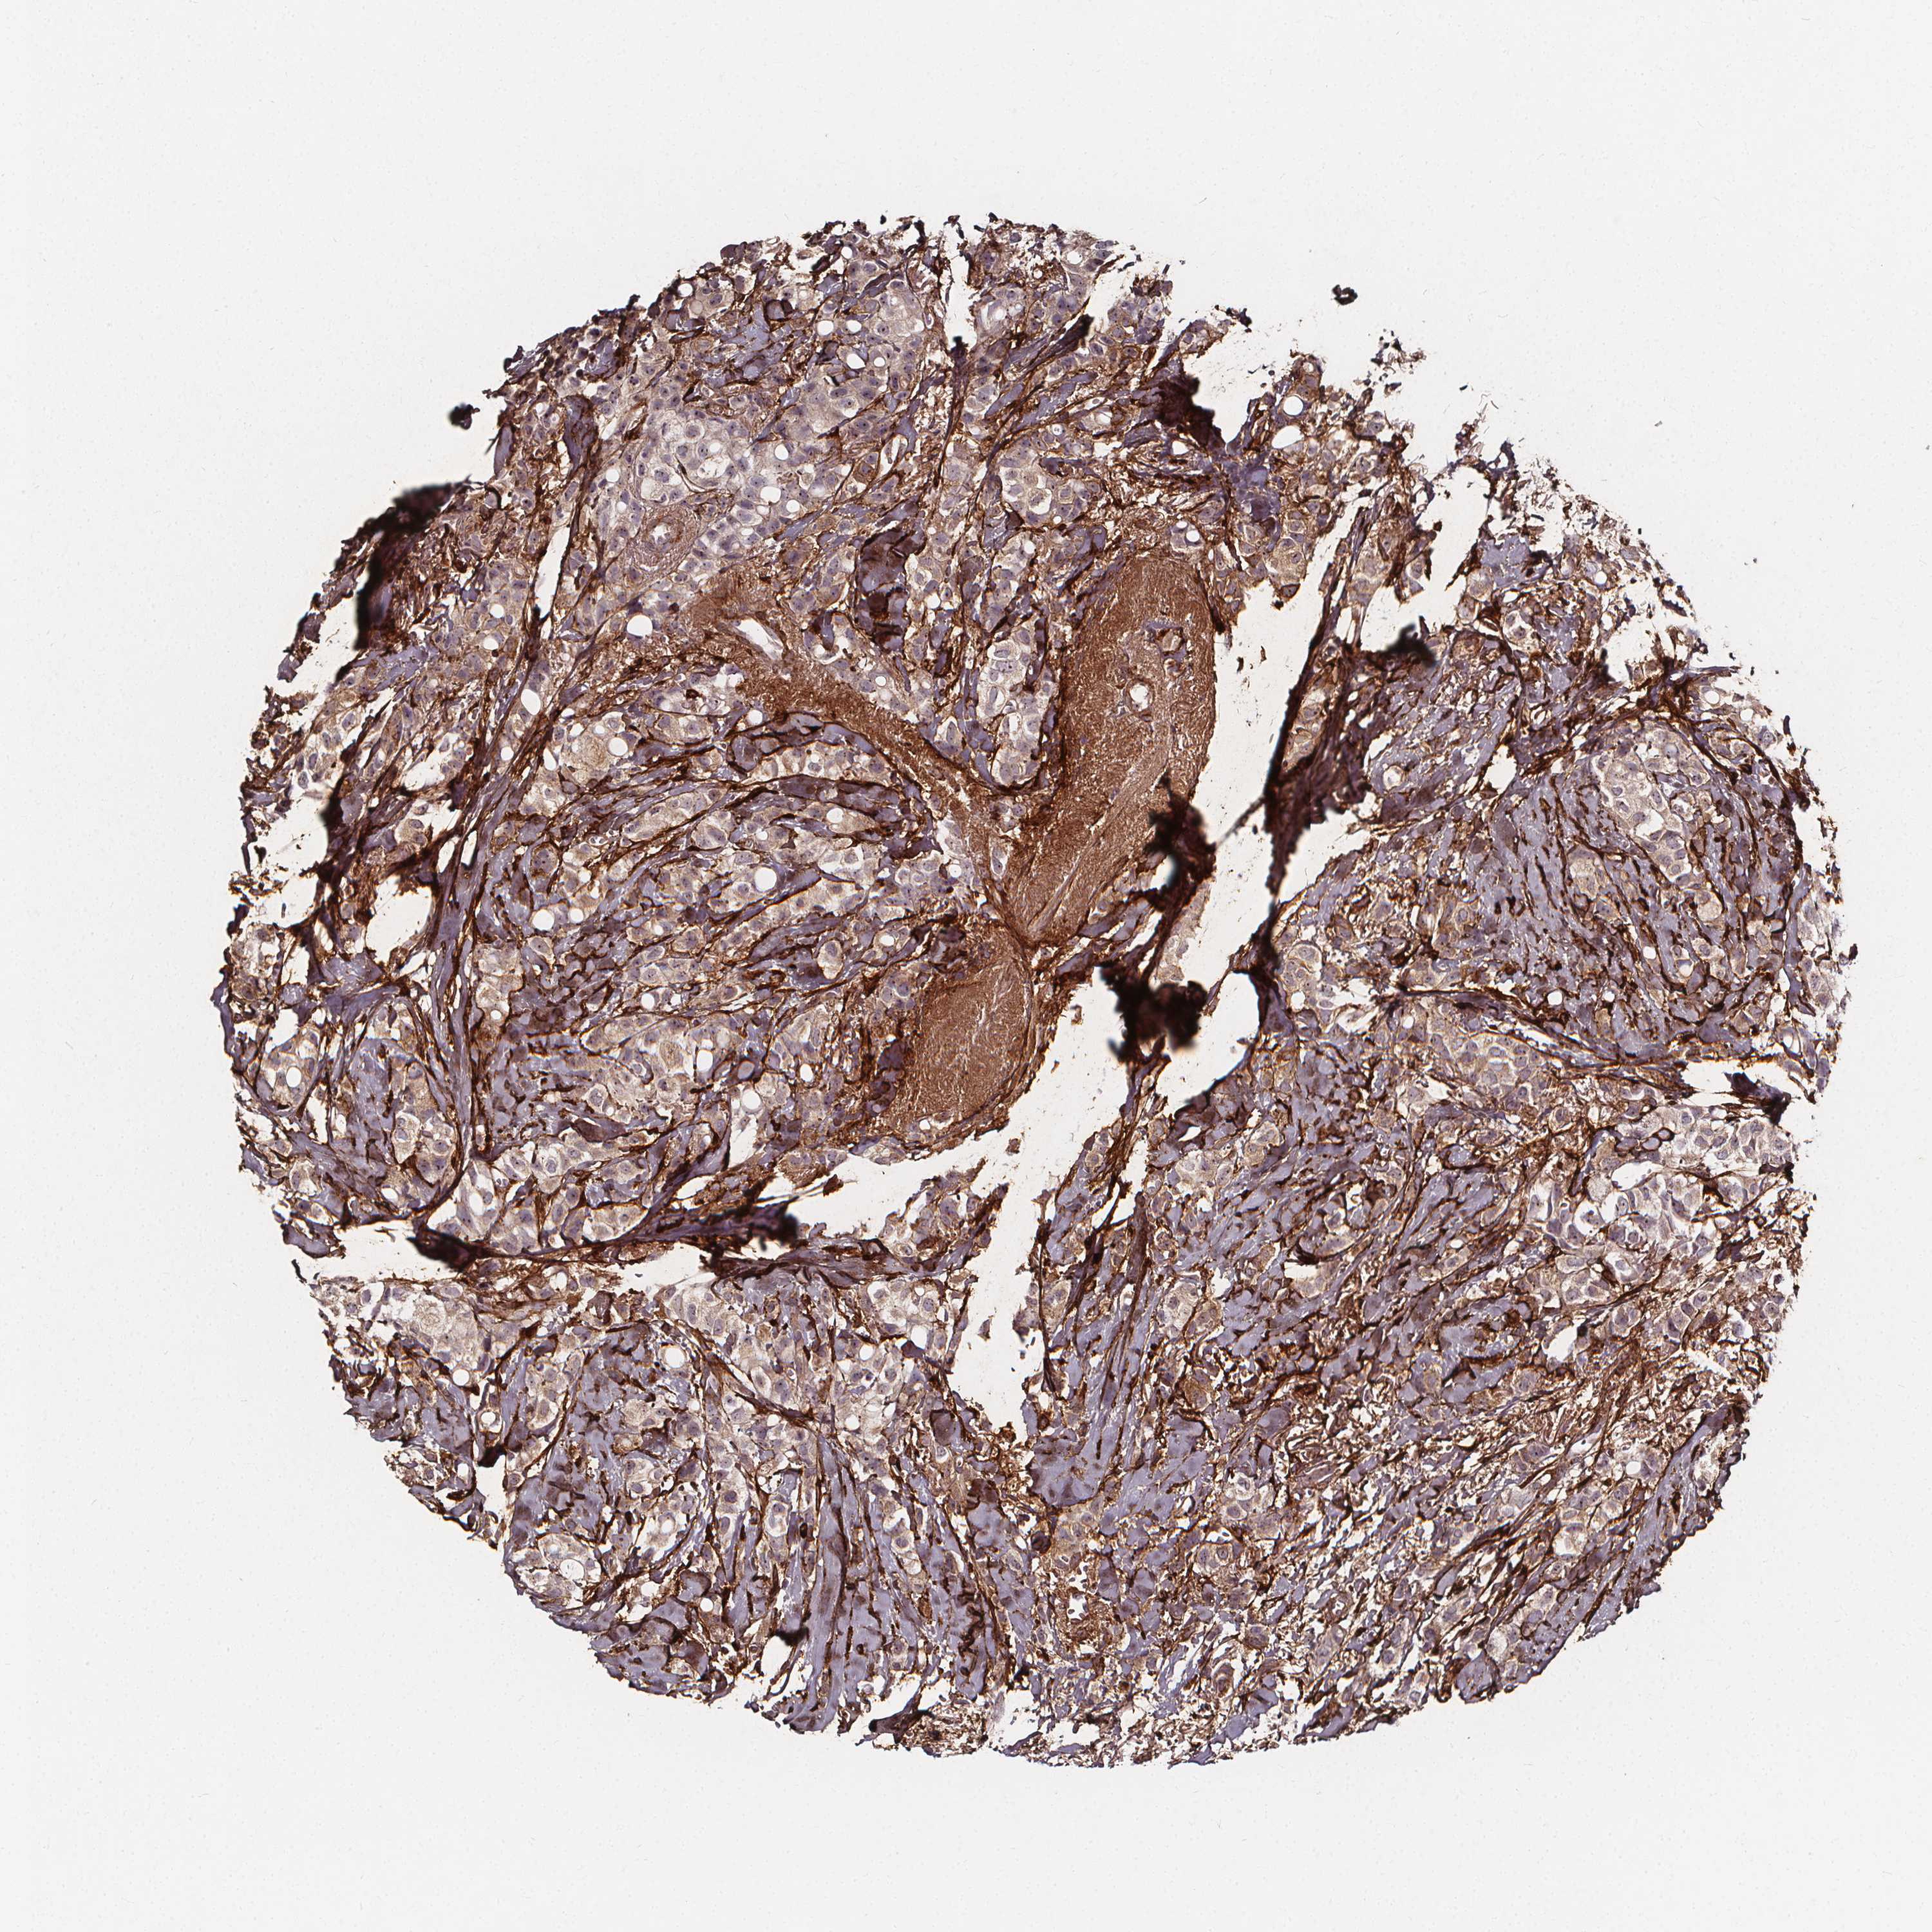

CANCER BREAST CANCER Show tissue menu

BRCA TCGA BRCA VALIDATION PROTEIN EXPRESSION

Breast cancer

Human cancer

Breast invasive carcinoma